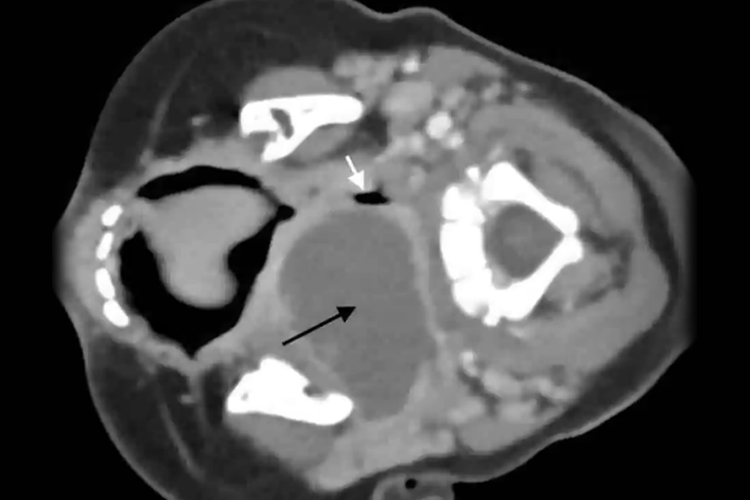

扁桃体脓肿:CT平扫可见咽后壁软组织肿胀并突向咽腔,致气道变形,与深部组织分界清或不清,增强呈不规则环形强化,脓腔无强化。结核性脓肿有时见脓肿壁钙化。